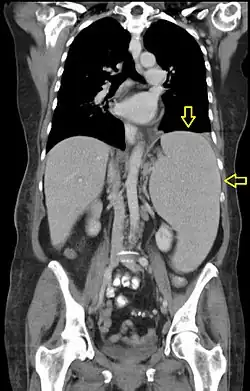

CT scan in a patient with chronic lymphocytic leukemia, showing splenomegaly. Yellow arrows point at the spleen.

To diagnose I-Cell Disease, specialists conduct a combination of clinical evaluations, biochemical tests, and genetic analyses. First, physicians consider the patient’s medical history for any symptoms like growth delays, coarse facial features, organ enlargement, or skeletal abnormalities. These initial examinations commonly reveal features like hepatosplenomegaly, joint stiffness, or dysostosis multiplex.[6]